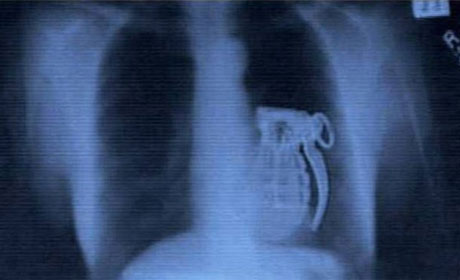

Mədəsindən əl bombası çıxdı - ŞOK FOTOLAR

İnsan nələri udmağa qadir deyil? Yaxud mədədən nələr gəlib-keçmir? ANN.Az-in oxuculara təqdim etdiyi fotolar bir daha insanın nələrə qadir olduğunu göstərir. 1. İlan balığı2. Qaşıq3. Batareyalar4. Canlı qurbağa5. Mismar6. Dərmanlar 7. Nişan üzüyü8. Qayçı9. Tük yumağı10. Mobil telefom11. Qələm12. Yay13. Əl bombası14. Açar15. Lampa